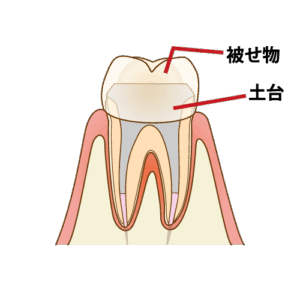

⏫⑥薬が浸透するのに、2〜3日様子を見て土台を立て被せ物の型取りをします。